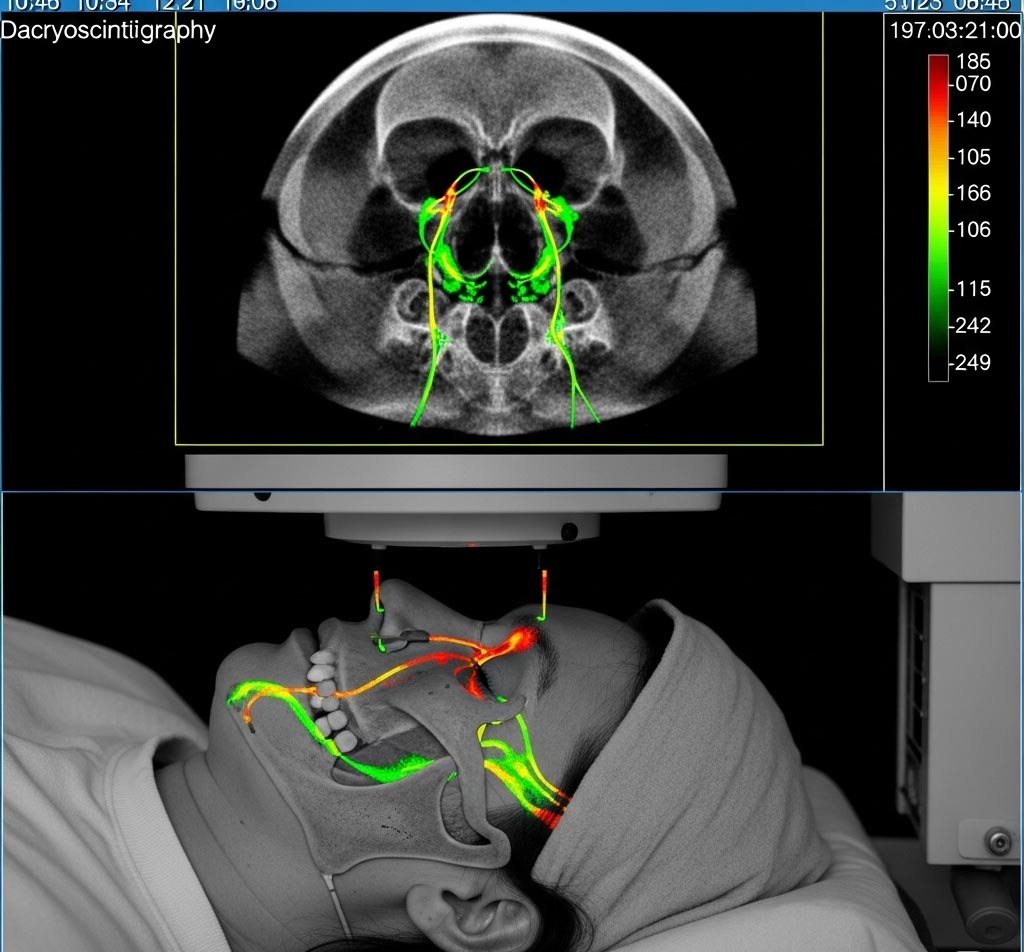

اسکن مجاری اشکی در تهران

اسکن مجاری اشکی چیست؟

در این روش، مقدار کمی ماده رادیواکتیو (معمولاً تکنسیوم-۹۹) به صورت قطره در چشم بیمار چکانده میشود. سپس با استفاده از دوربین گاما، مسیر عبور اشک از چشم تا حلق بررسی میشود. اگر مجرا بسته یا کند باشد، ماده رادیواکتیو در چشم باقی میماند و تخلیه نمیشود.